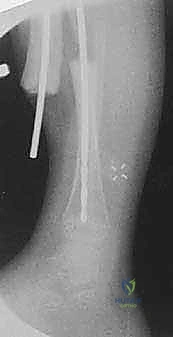

الخطوة الرابعة: تجهيز القناة النخاعية

باستخدام أدوات حفر دقيقة (Reamers)، يتم فتح وتوسيع القناة النخاعية المسدودة في كل من الجزء العلوي والسفلي لقصبة الساق. يجب أن يكون الحفر دقيقاً لإنشاء مسار مستقيم يسمح بمرور القضيب المعدني.

الخطوة الخامسة: إدخال قضيب ويليامز

يتم اختيار قضيب ويليامز بالطول والسمك المناسبين بناءً على قياسات دقيقة. يتم إدخال القضيب من أعلى قصبة الساق (قرب الركبة) أو من أسفلها، ليخترق القناة النخاعية، ويعبر منطقة الكسر، ليصل إلى الجزء الآخر من العظم، مما يضمن استقامة الساق وتثبيت الكسر بقوة.